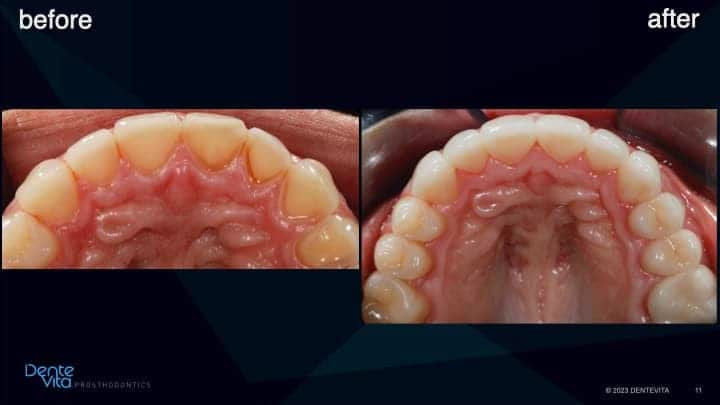

Tooth enamel wear and erosion, with resultant short/smaller teeth dimensions and associated vertical and horizontal tooth drift.

Teeth wear/erosion results in missing tooth structure. When this occurs, teeth naturally vertical/horizontally drift in order for the teeth to re-establish contact with the opposing or adjacent teeth, thereby enabling us to chew food effectively. However, if we would like to establish correct tooth length/dimensions once again, this is challenging to perform, especially in a conservative manner, since restorative space is lost.

One option to reverse tooth drift is by utilizing pre-orthodontic treatment solutions to intrude/translate affected teeth, thereby re-establishing correct tooth position, gum-line positions, and re-capture vertical/horizontal restorative space for future teeth rehabilitation/restoration.

This case study addressed significant tooth erosion from gastric reflux. Lost vertical space from vertical tooth drift was reversed with orthodontic treatment (intrusion and alignment therapy).

After completion of successful orthodontic therapy, missing tooth structure was rehabilitated/restored with conservative 360 degree and three-quarter porcelain veneer therapy, along with posterior occlusal partial coverage onlay restorations.